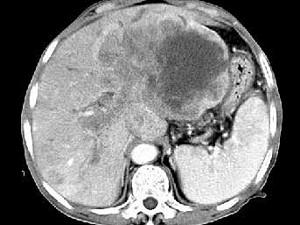

问题 女,73岁,中上腹痛一月余,患者黄疸、消瘦,CT检查如下图,最可能的诊断是 ( )

选项 A、肝淋巴管瘤 B、肝胆管细胞癌 C、巨块型肝癌 D、肝血管瘤 E、肝脓肿

答案 C